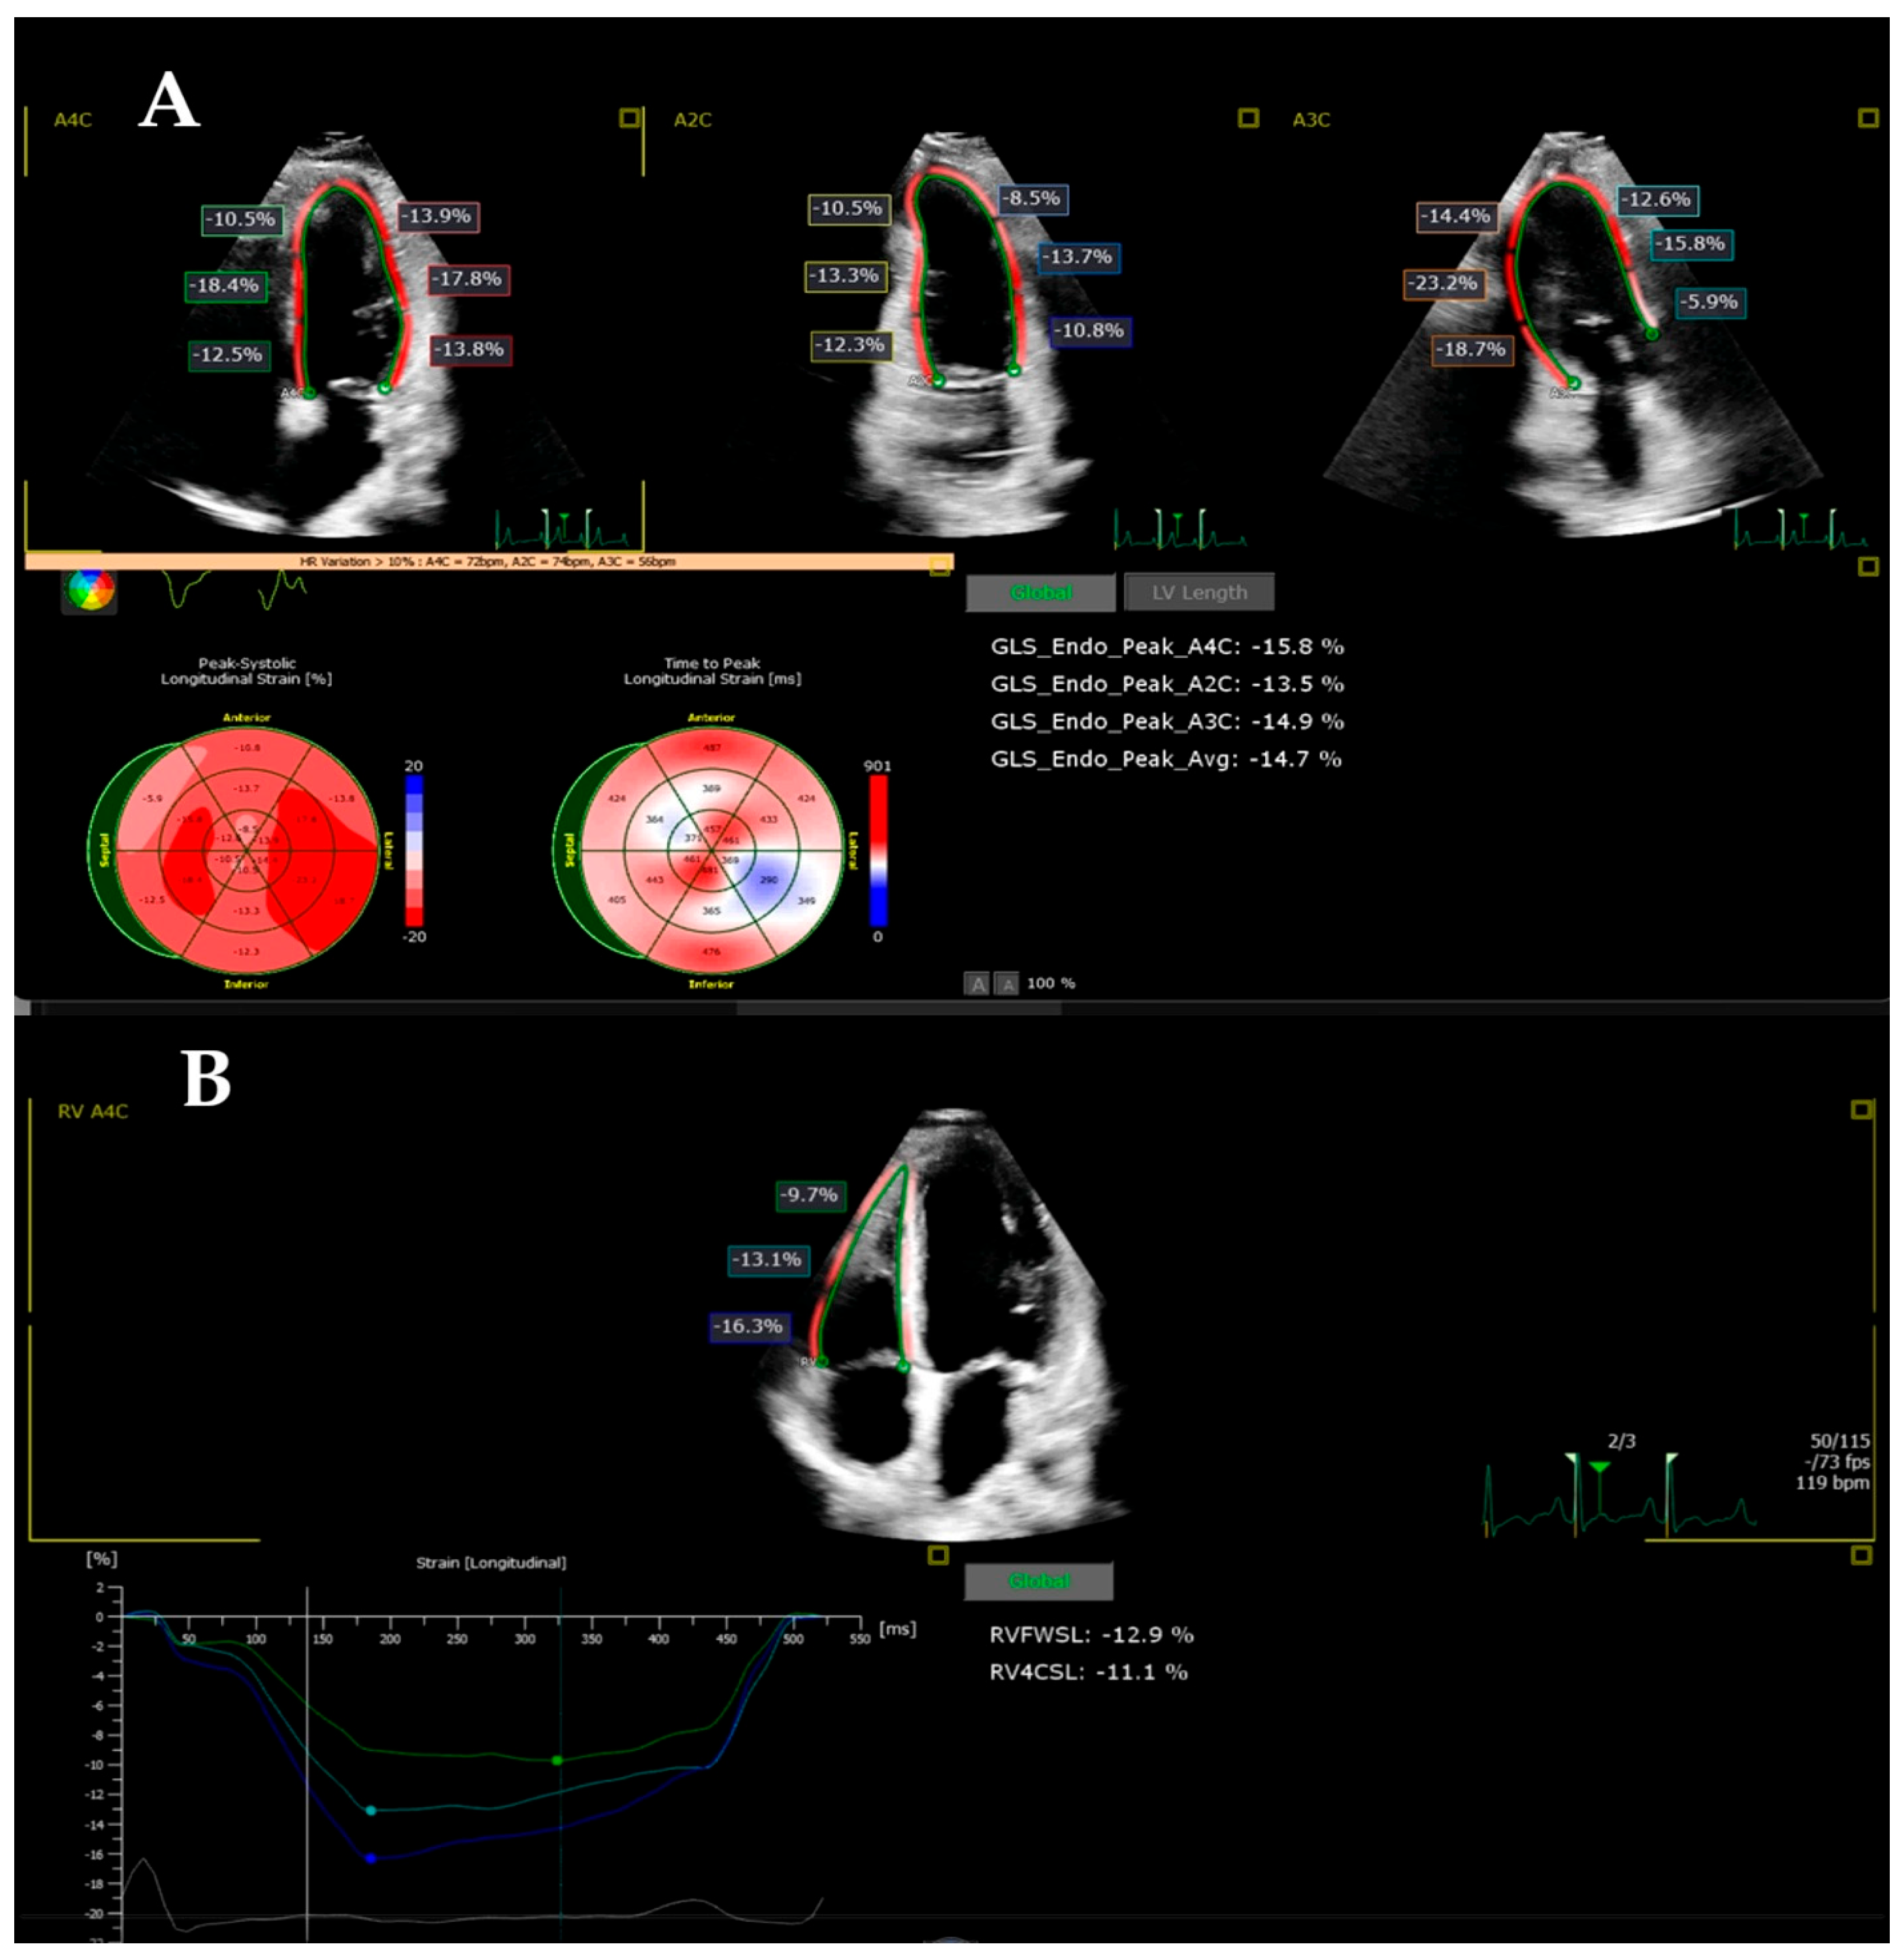

2.3. Strain Imaging

3.2. Follow-Up of the Echocardiographic Strain Indices in the MIS-C Patients (DWD Versus DD)

3.3. The Impact of LV EF on the Echocardiographic Strain Indices

| LV GLS (%) | −24.23 ± 2.23 | −15.45 ± 4.76 | −20.63 ± 4.66 | 0.0001 | 0.014 | 0.0001 |

| RVFWLS (%) | −27.13 ± 13.37 | −21.94 ± 7.86 | −25.90 ± 6.76 | 0.248 | 1.000 | 0.549 |

| RV4CLS (%) | −23.90 ± 10.77 | −18.30 ± 9.90 | −21.34 ± 10.87 | 0.248 | 1.000 | 1.000 |

| LV GLS (%) | −24.23 ± 2.23 | −17.94 ± 4.68 | −13.39 ± 3.90 | 0.0001 | 0.0001 | 0.009 |

| RVFWLS (%) | −27.13 ± 13.37 | −24.46 ± 6.81 | −19.84 ± 8.33 | 1.000 | 0.214 | 0.995 |

| RV4CLS (%) | −23.90 ± 10.77 | −21.69 ± 4.99 | −15.49 ± 12.16 | 1.000 | 0.081 | 0.494 |

| BIS LS (%) | −23.51 ± 4.02 | −18.16 ± 7.58 | −13.36 ± 4.41 | 0.027 | 0.0001 | 0.103 |

| MIS LS (%) | −25.45 ± 4.10 | −17.72 ± 4.83 | −15.85 ± 5.38 | 0.0001 | 0.0001 | 1.000 |

| AIS LS (%) | −25.62 ± 5.33 | −18.39 ± 6.33 | −12.88 ± 3.09 | 0.002 | 0.0001 | 0.047 |

| BAL LS (%) | −26.12 ± 5.56 | −21.21 ± 11.10 | −15.68 ± 6.25 | 0.256 | 0.001 | 0.255 |

| MAL LS (%) | −22.13 ± 3.85 | −17.07 ± 4.14 | −14.10 ± 5.56 | 0.014 | 0.0001 | 0.380 |

| AAL LS (%) | −25.20 ± 4.86 | −16.72 ± 4.95 | −14.05 ± 4.73 | 0.0001 | 0.0001 | 0.622 |

| BRV LS (%) | −33.55 ± 5.32 | −25.10 ± 7.43 | −22.80 ± 8.46 | 0.006 | 0.0001 | 1.000 |

| MRV LS (%) | −28.68 ± 4.55 | −23.20 ± 6.69 | −19.37 ± 8.06 | 0.074 | 0.0001 | 0.463 |

| ARV LS (%) | −26.24 ± 4.55 | −22.94 ± 6.55 | −14.97 ± 11.59 | 0.762 | 0.0001 | 0.052 |

| LV GLS (%) | −24.23 ± 2.23 | −23.34 ± 2.84 | −18.37 ± 4.76 | 1.000 | 0.0001 | 0.003 |

| RVFWLS (%) | −27.13 ± 13.37 | −28.09 ± 6.13 | −24.09 ± 6.97 | 1.000 | 1.000 | 1.000 |

| RV4CLS (%) | −23.90 ± 10.77 | −25.87 ± 3.40 | −17.57 ± 13.50 | 1.000 | 0.304 | 0.219 |

| BIS LS (%) | −23.51 ± 4.02 | −23.59 ± 8.72 | −16.80 ± 5.79 | 1.000 | 0.008 | 0.029 |

| MIS LS (%) | −25.45 ± 4.10 | −17.80 ± 13.54 | −19.11 ± 5.77 | 0.035 | 0.075 | 1.000 |

| AIS LS (%) | −25.62 ± 5.33 | −23.25 ± 7.85 | −18.51 ± 5.72 | 0.932 | 0.007 | 0.228 |

| BAL LS (%) | −26.12 ± 5.56 | −27.96 ± 10.52 | −22.80 ± 10.23 | 1.000 | 0.807 | 0.457 |

| MAL LS (%) | −22.13 ± 3.85 | −22.44 ± 5.41 | −15.82 ± 6.98 | 1.000 | 0.005 | 0.015 |

| AAL LS (%) | −25.20 ± 4.86 | −20.76 ± 5.22 | −18.09 ± 4.67 | 0.066 | 0.001 | 0.631 |

| BRV LS (%) | −33.55 ± 5.32 | −29.09 ± 8.48 | −26.56 ± 8.59 | 0.317 | 0.026 | 1.000 |

| MRV LS (%) | −28.68 ± 4.55 | −26.19 ± 4.32 | −24.00 ± 8.46 | 0.806 | 0.092 | 1.000 |

| ARV LS (%) | −26.24 ± 4.55 | −26.33 ± 5.15 | −21.40 ± 8.59 | 1.000 | 0.092 | 0.190 |